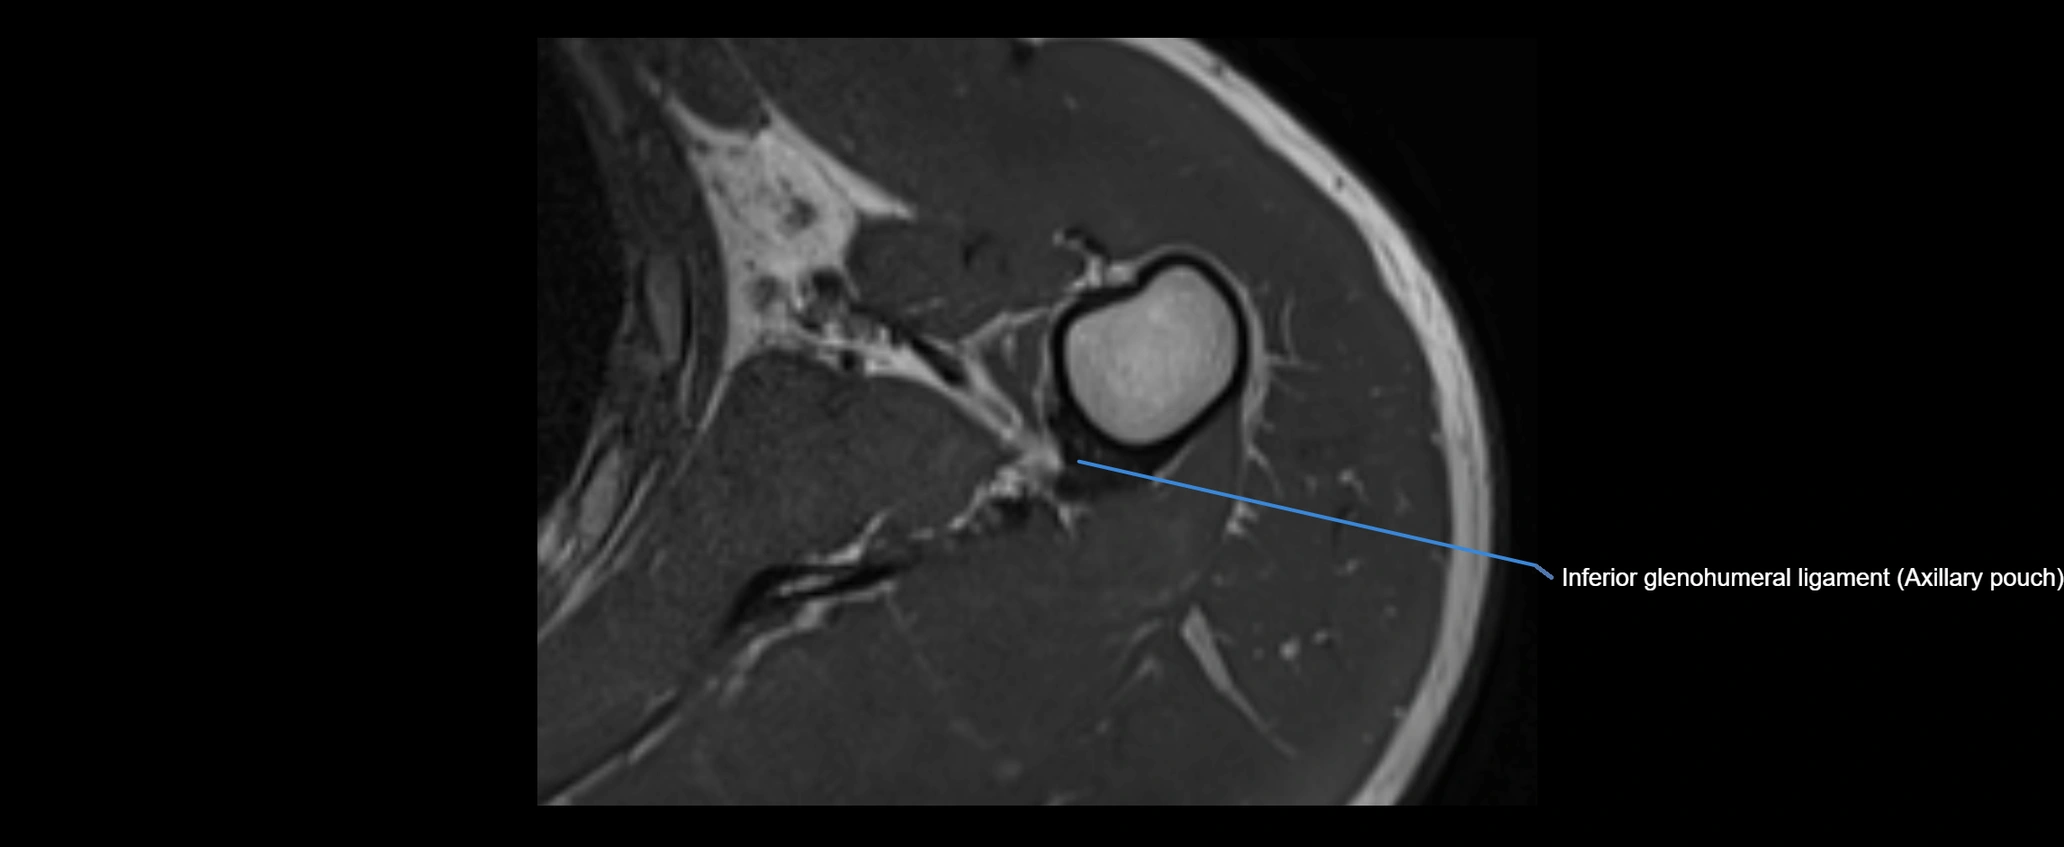

MRI images

image